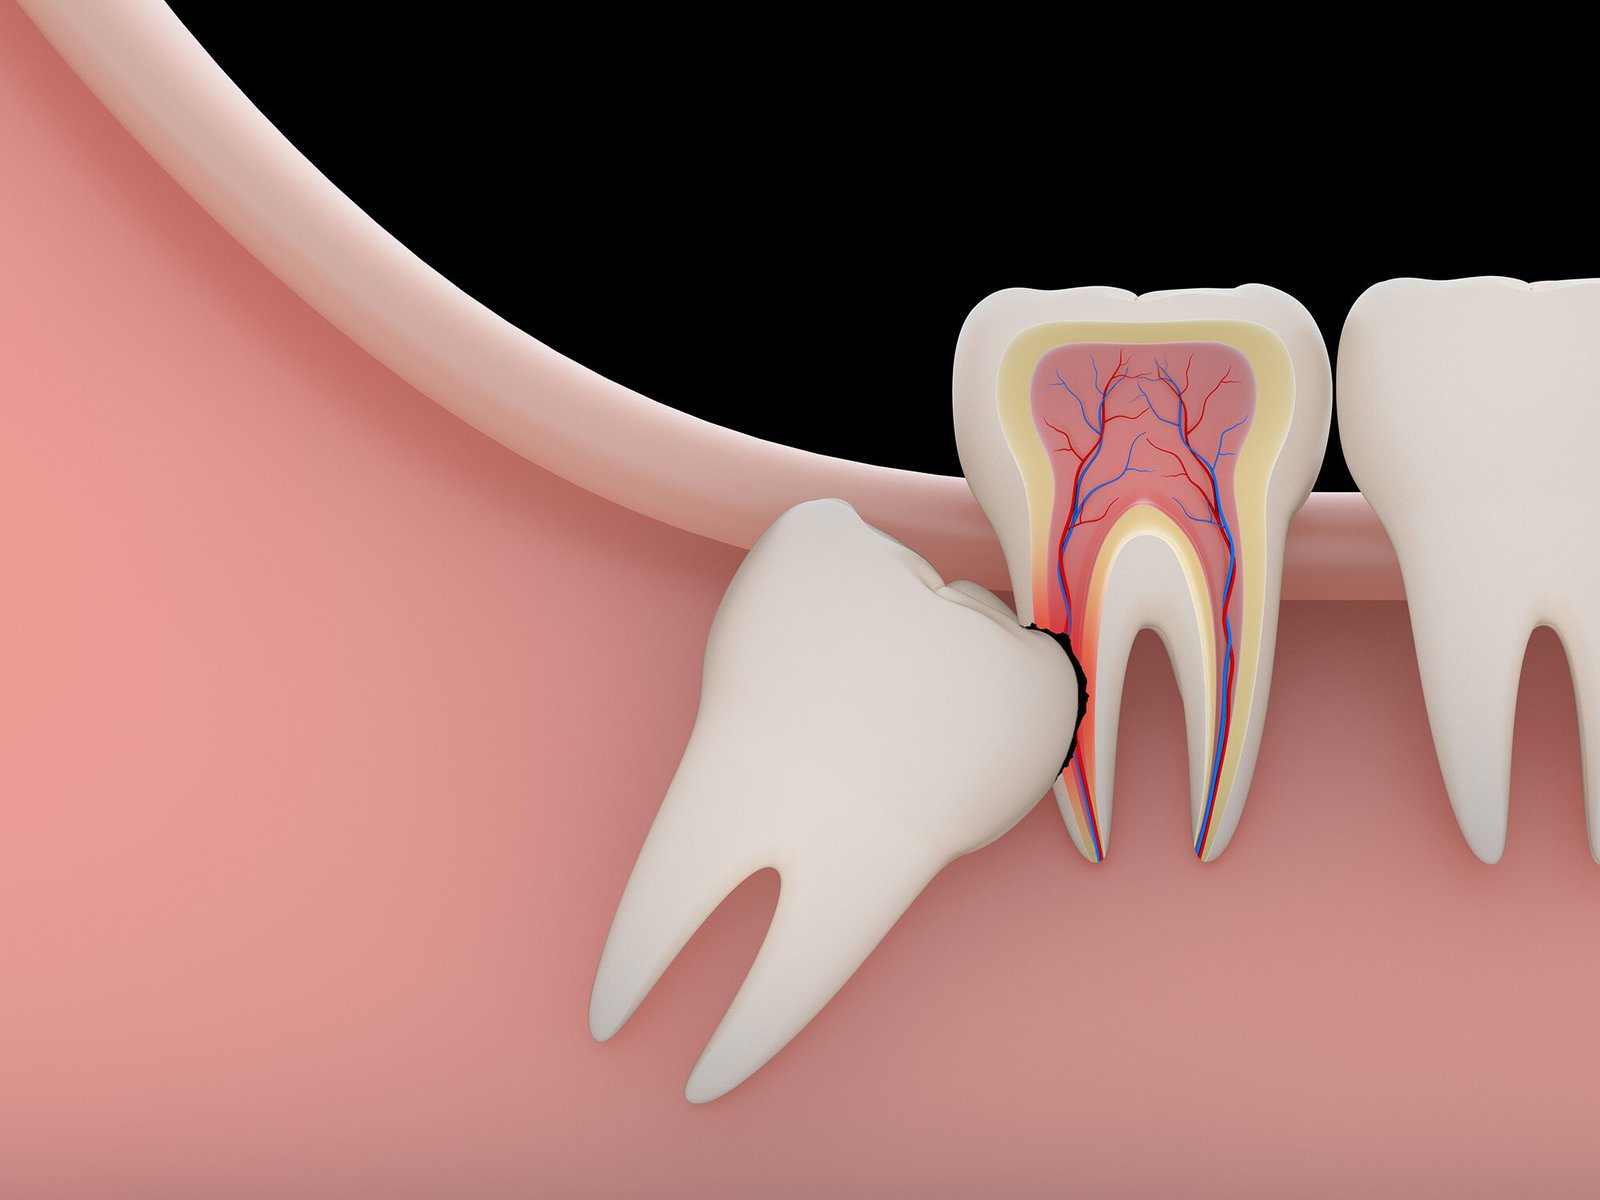

Wisdom tooth is the last tooth that has erupted in the dental arch. The proper time of eruption is around 18-25 years. There are around 4 wisdom teeth, 1 in each arch.

Why is it necessary to remove a wisdom tooth?